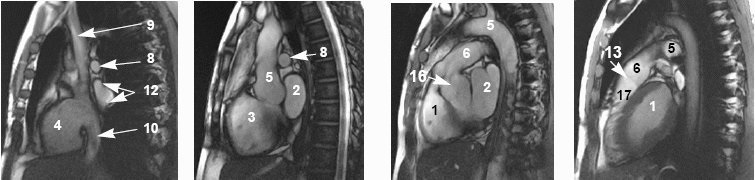

Cardiac anatomy

View an image plane and refer to the legend below for the corresponding cardiac anatomy.

| Cardiac anatomy image legend | |||

|---|---|---|---|

| 1 = left ventricle

2 = left atrium 3 = right ventricle 4 = right atrium | 5 = aorta

6 = pulmonary artery 7 = left pulmonary artery 8 = right pulmonary artery | 9 = superior vena cava

10 = inferior vena cava 12 = right pulmonary vein 13 = pulmonary valve | 14 = tricuspid valve

15 = mitral valve 16 = aortic valve 17 = ventricular outflow tract |